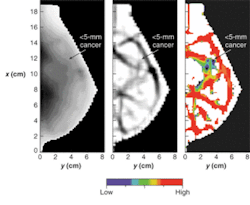

To get beyond the depth-of-penetration limitations of OCT, diffuse optical imaging (also known as photon-migration imaging) takes advantage of a "spectral window" in human tissue from about 700 to 900 nm in which light absorption due to chromophores such as blood and water is relatively weak. Scattering effects remain strong within this window, however, generally causing light to "diffuse" in a manner that can be modeled, in the brain and breast for instance, by Monte Carlo representations of the diffusion equation and by analytic expressions (see Fig. 3).2, 3, 4Near-IR radiation enables visualization of the oxygen state of hemoglobin as well as the amount of blood flowing through muscle, brain, and breast tissue, according to optical-imaging pioneer Britton Chance, currently an emeritus faculty member at the University of Pennsylvania (Philadelphia, PA). "Blood is our main signal," he said. "There are other signals, like water and lipid, that are not really functional. This is functional near-IR imaging, however, because the blood responds to function."